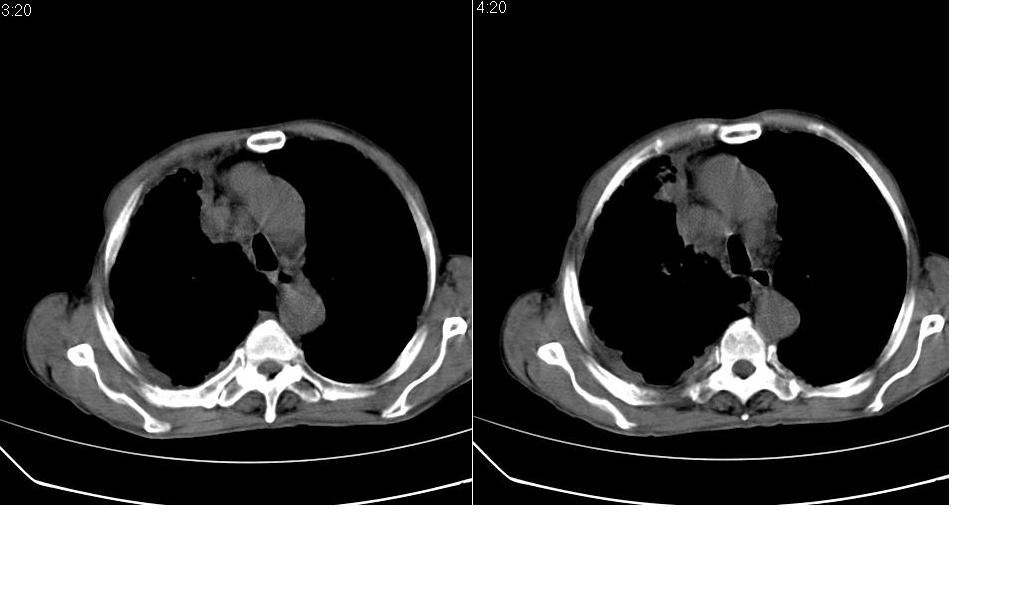

以下是引用zsl6918在2008-5-3 19:53:00的发言:[br]右肺中心型肺癌并纵隔淋巴结转移,胸膜转移,右肺癌性淋巴管炎。

以下是引用liuyue在2008-5-3 20:49:00的发言:[br]1.右侧中心型肺癌伴双肺转移瘤、纵隔淋巴结转移、右侧胸腔积液(侵及胸膜所致可能性大)。[br]2.右肺阻塞性肺炎,癌性淋巴管炎不除外。